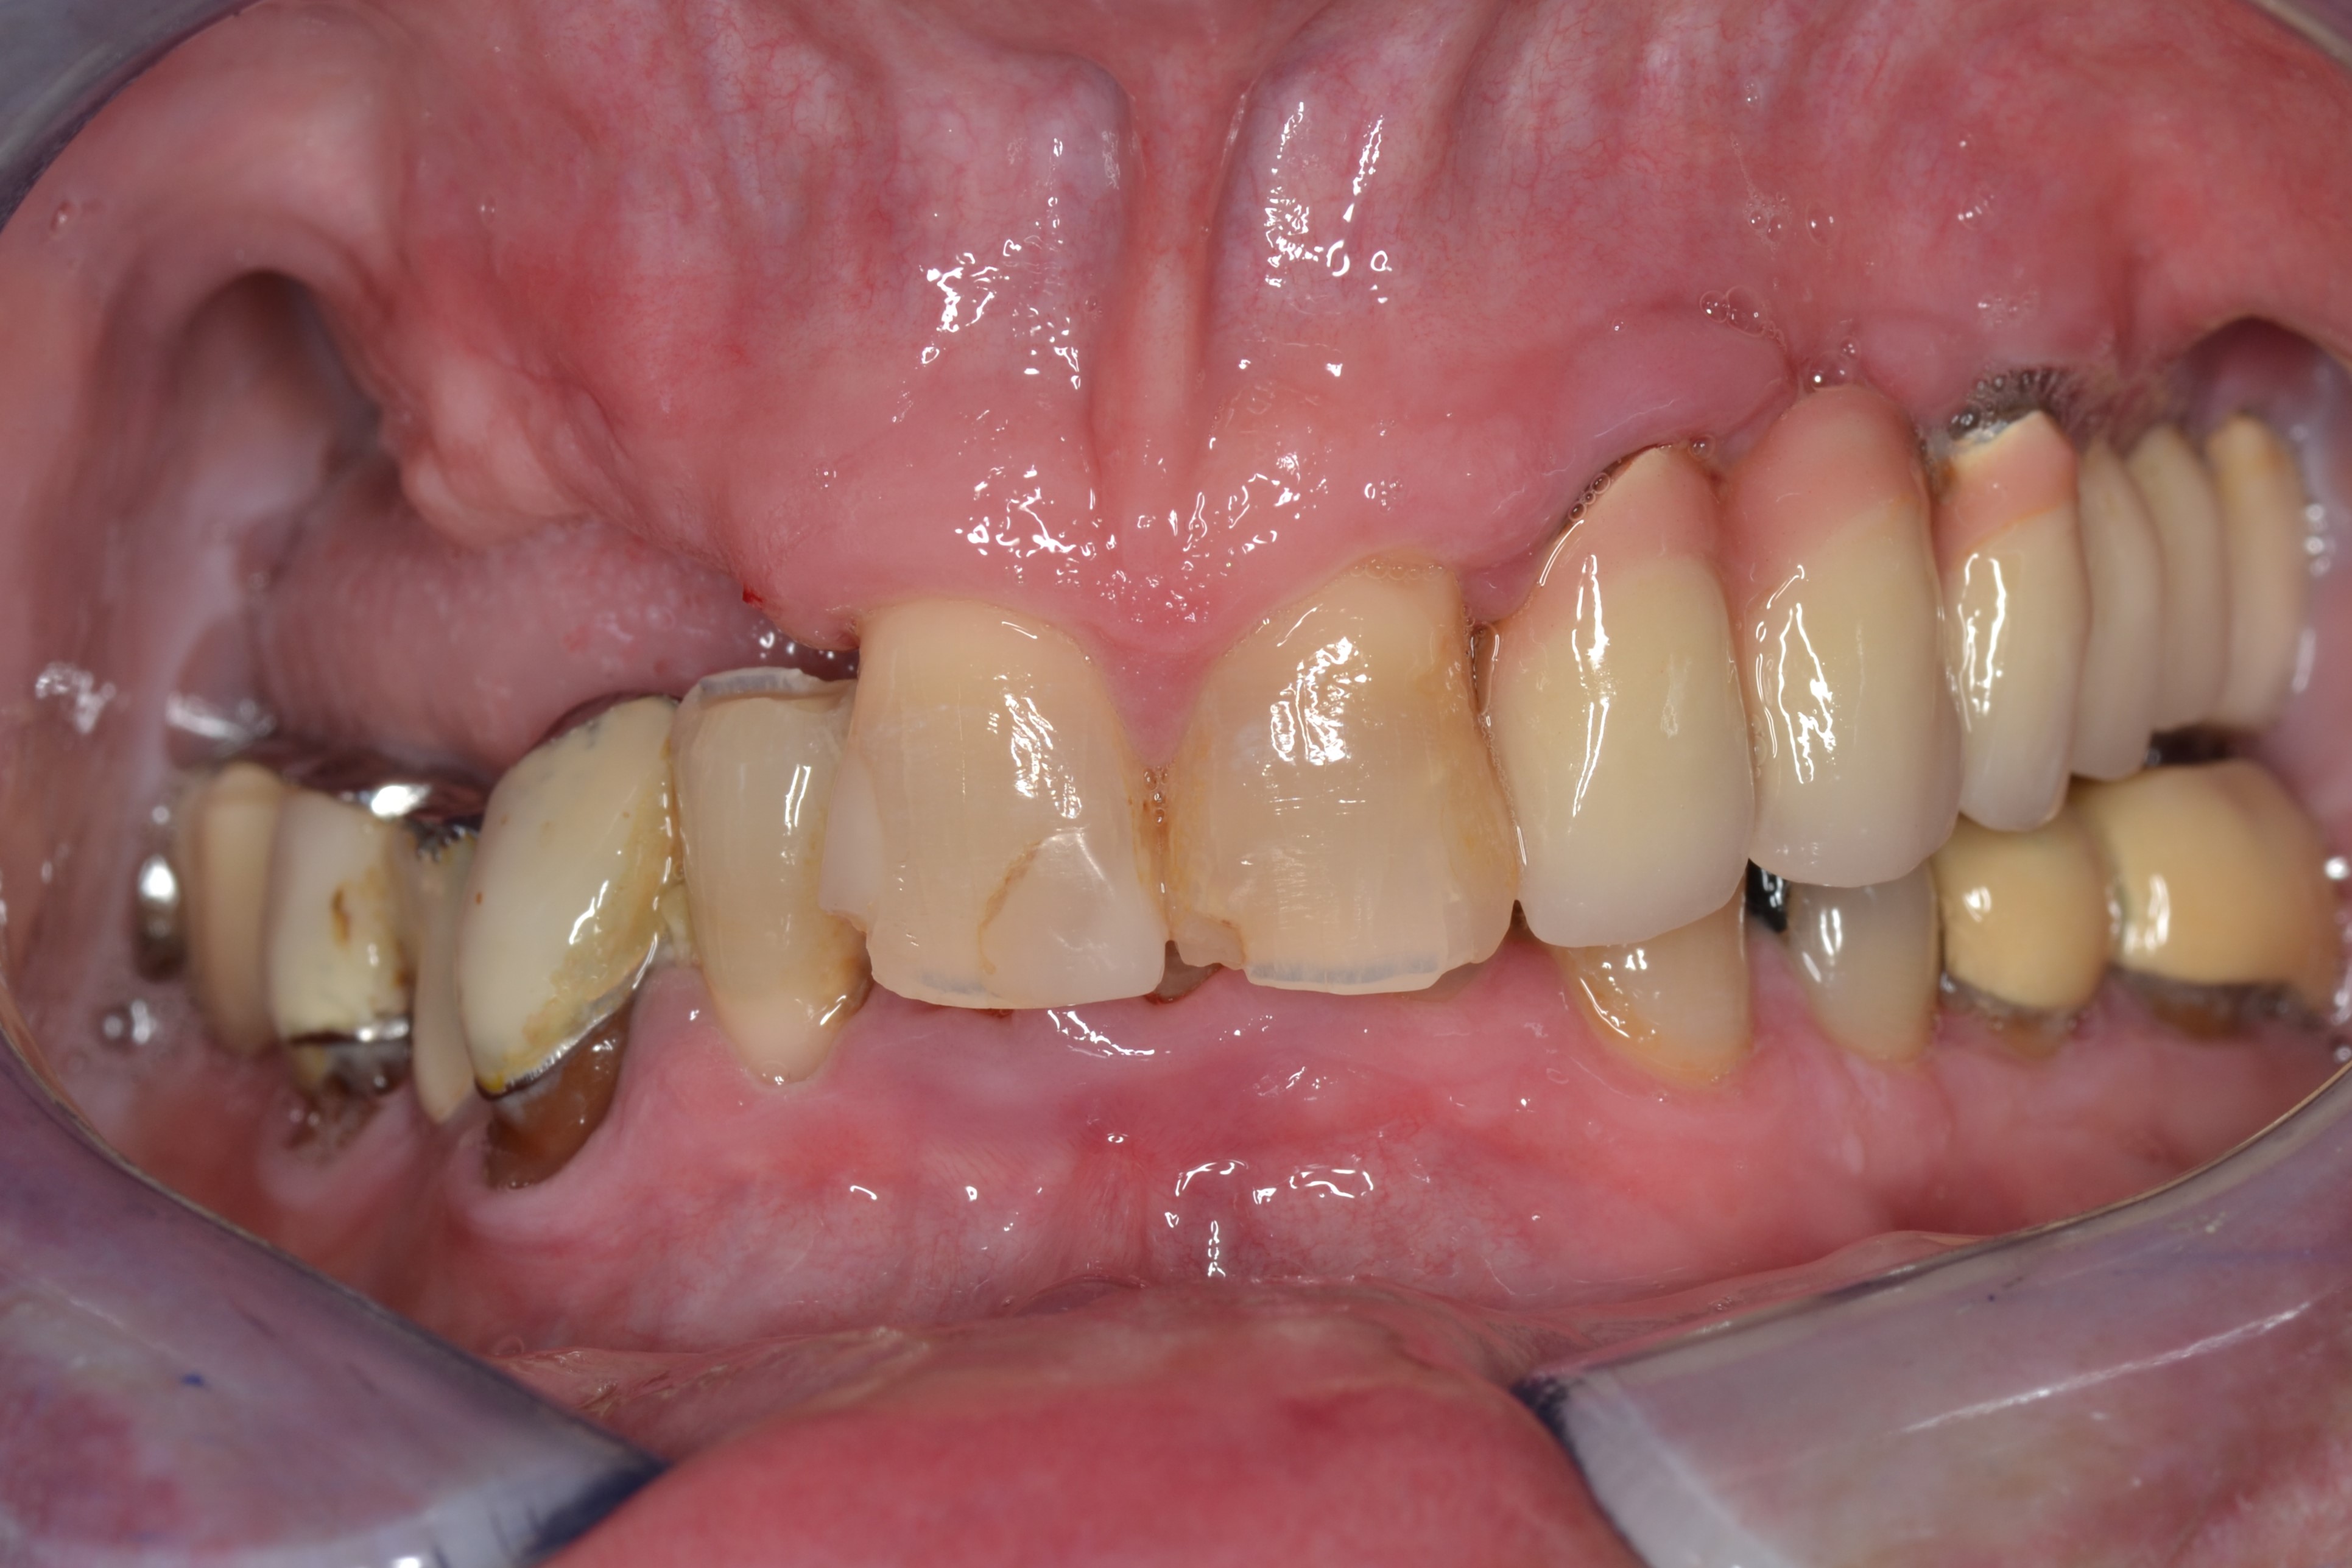

Ο 81-χρονος αυτός ασθενής μας προσήλθε στο ιατρείο με μερικά ελλείποντα δοντια στην άνω γνάθο και σπασίματα στα πρόσθια δόντια.

Πάρθηκε ψηφιακό αποτύπωμα με τον σαρωτή TRIOS και του κατασκευάσαμε μια μερική οδοντοστοιχία με μεταλλικά βαμμένα άγκιστρα στην άνω γνάθο για να αποκαταστήσουμε τα δοντια που έλλειπαν.

Επίσης, το σχήμα των προσθίων δοντιών αποκαταστάθηκε με σφραγίσματα συνθετικής ρητίνης.